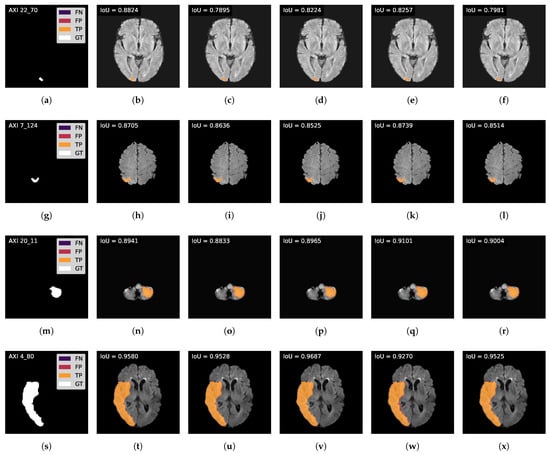

A visual comparison between the model’s version is given in Figure 5 to complement this ablation test. The results are ordered following the mask’s size categories: Small (first row), Medium Down (second row), Medium Up (third row), and Large (fourth row). The cases are identified in the ground truth mask image using the nomenclature P C_S, where P refers to the plane, C to the subject’s case number, and S to the slice. This figure shows slight differences in the number of FP and FN pixels: the Dice Loss and W/O A.M. versions present more FP pixels than the proposed model, while Focal Loss results in a narrowly higher number of FN. Furthermore, the CBAM model introduced more FP than the proposed approach but less than the W/O A.M. model, as seen in the case AXI 4_80.

Figure 5. Visual comparison of the model’s versions results: Ground truth masks are displayed in the first column (a,g,m,s). Results of Proposed model are given in the second column (b,h,n,t), of Dice Loss model in the third column (c,i,o,u), of Focal Loss model in the fourth column (d,j,p,v), of W/O A.M. model in the fifth column (e,k,q,w), and of CBAM model in the sixth column (f,l,r,x).